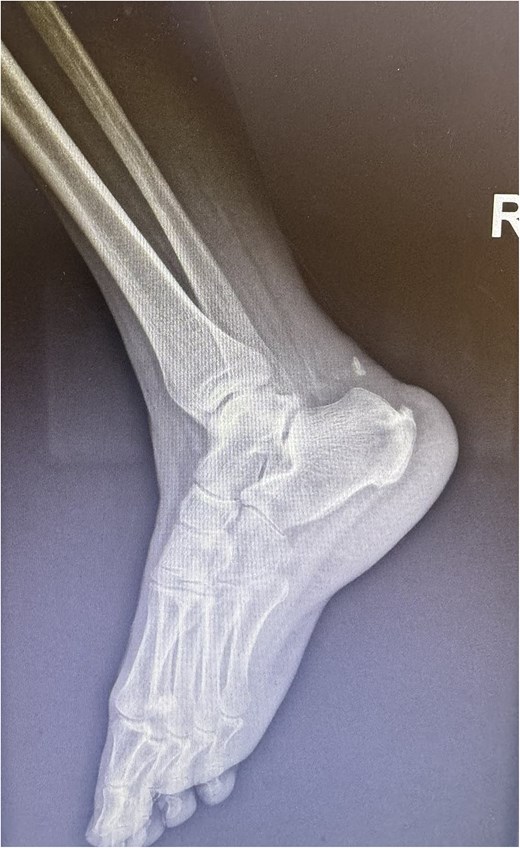

A 68-year-old female presented to the emergency department with significant discomfort localized to the Achilles tendon region. Her medical history was relatively uneventful, except for hypothyroidism and a previous diagnosis of Achilles tendinopathy (Fig. 1), that was treated conservatively with ten daily sessions of percussive ultrasound therapy. More specifically radial extracorporeal shockwave therapy (ESWT) was used, with 2.000 shockwaves at 12 Hz, which was followed by physical therapy exercises and ice therapy. Following the therapeutic sessions, the patient experienced acute symptoms, including a pronounced popping sensation and significant functional impairments.

A comprehensive physical examination provided significant insights into the patient’s condition following the Achilles tendon rupture. The Thompson test was particularly noteworthy, showing an absence of plantar flexion upon calf compression, strongly indicating a complete tendon rupture. The examination further revealed a palpable gap in the Achilles tendon and increased passive dorsiflexion. Symptoms included significant weakness, difficulty walking and heel pain. Imaging studies, including X-rays (Fig. 2) and magnetic resonance imaging (MRI) (Fig. 3), confirmed these findings, showing an acute rupture with retracted tendon edges, distinguishing it from chronic condition and suggesting a possible link to the vigorous ultrasound therapy [3].